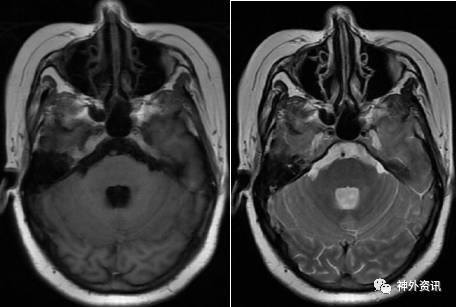

术后5月,患者诉头痛、呕吐来门诊复诊,复查头颅MRI平扫加增强显示:左顶叶,右小脑半球,第三、四脑室,鞍上池见斑片状长T1、长T2信号影,增强后明显强化;左侧小脑半球及桥脑脚大片T1低信号,T2高信号影,强化后桥臂病灶明显强化,同时可见桥脑腹侧面片状软脑膜增强影。诊断:脑内多发强化灶伴局部软脑膜强化,考虑转移瘤可能(图7)。

图7. MRI检查:左顶叶,右小脑半球,第三、四脑室,鞍上池见斑片状长T1、长T2信号影,增强后明显强化。